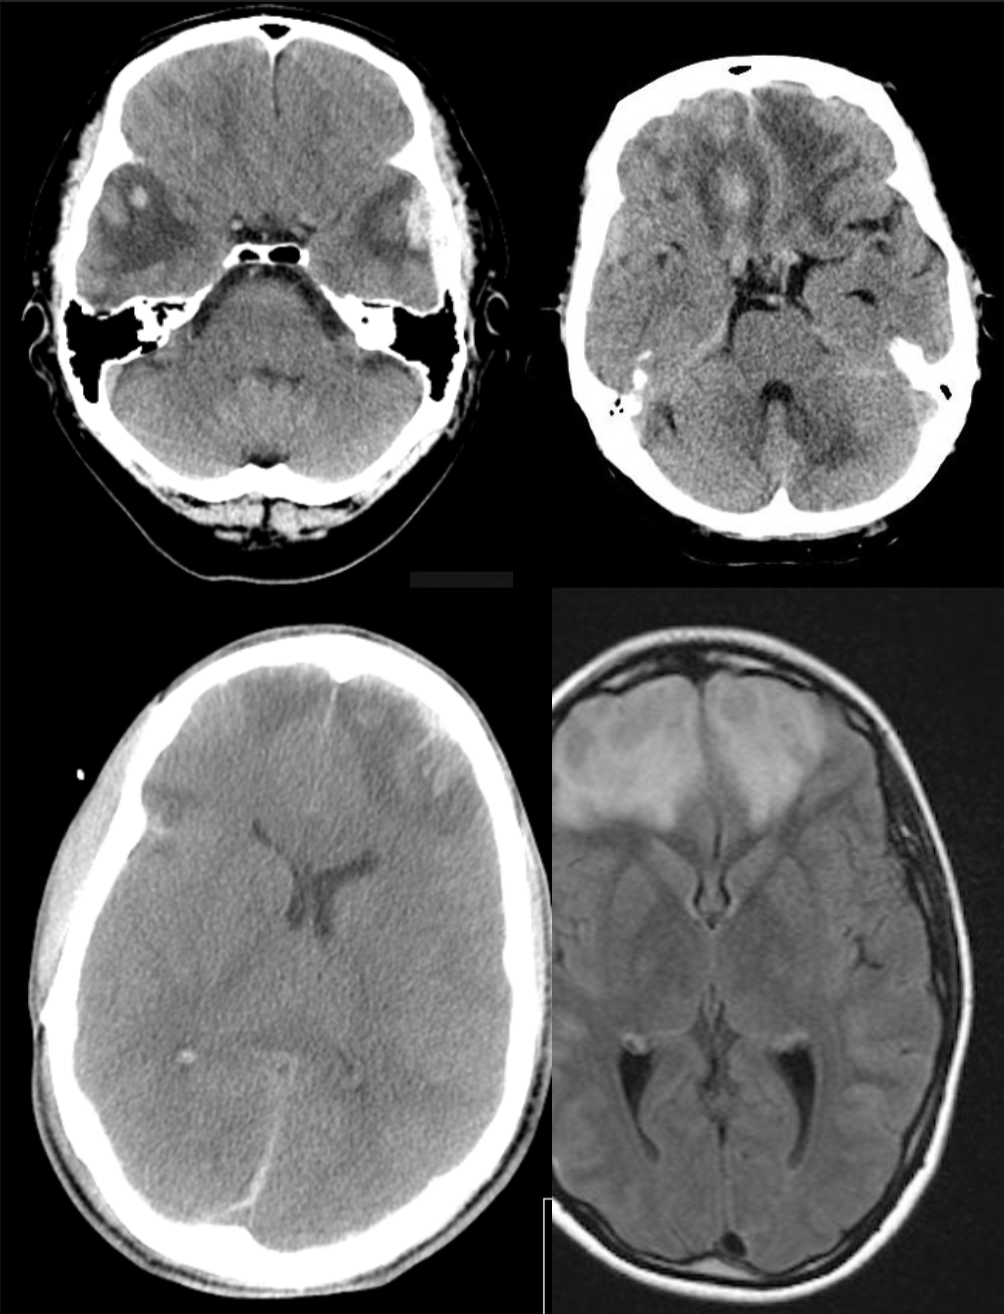

A 43 year-old man with a headache and lethargy after a car accident.

Subarachnoid hemorrhage

43 year-old man after trauma.

Cerebral contusion (intraparenchymal hemorrhage)